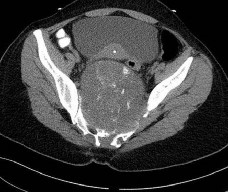

A 55-year-old patient with poorly controlled type II diabetes presents with a red, hot, swollen right foot. Inflammatory markers are normal and an MRI confirms no osteomyelitis. Radiographs reveal prominent periarticular osseous debris, fragmentation of the navicular and cuneiforms, and subluxation of the tarsometatarsal joints. According to the Eichenholtz classification of Charcot arthropathy, what stage does this clinical and radiographic picture represent?

Explanation

The Eichenholtz classification describes the natural history of Charcot arthropathy. Stage 0 is the acute inflammatory stage without radiographic changes. Stage I (Development/Fragmentation) is characterized clinically by a hot, swollen foot and radiographically by osteopenia, periarticular fragmentation, bony debris, and subluxation/dislocation. Stage II (Coalescence) shows absorption of fine debris, fusion of larger fragments, and early sclerosis. Stage III (Consolidation) shows remodeling, rounding of bone ends, and stable deformity.